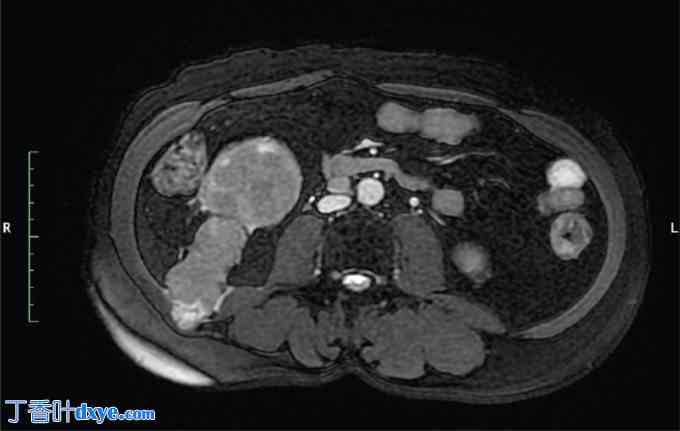

一位54岁男性患者,既往无其他疾病,因右侧腰痛就诊。非增强CT检查证实其肾盂内有鹿角状结石,未见可疑肿块。随后,患者接受了两次经皮肾镜取石术(PCNL),直至结石完全取出。术后3个月,患者持续出现右侧腰痛和偶发性血尿,遂转诊至院。进一步行增强CT和磁共振成像(MRI)检查,发现右肾内存在一强化病灶,从肾盂延伸至PCNL手术通道,并伴有腔静脉后、主动脉腔静脉和腔静脉前淋巴结肿大(图1-4)。CT引导下穿刺活检证实为高级别鳞状分化癌。血尿素氮为30 mg/dL,肌酐为1.2 mg/dL,钙为9.2 mg/dL,磷酸盐为3 mg/dL。尿细胞学检查发现发育不良细胞,二乙烯三胺五乙酸(DTPA)检查显示患侧肾脏肾小球滤过率降低至20 mL/min,未见其他部位转移。因此,患者接受了根治性肾切除术,同时整块切除了两个经皮肾镜取石术(PCNL)通道、受累皮肤和侧腹肌,并进行了基于模板的腹膜后淋巴结清扫术,随后进行了网片重建。术后恢复顺利。最终的组织病理学检查结果显示,肾脏大小为15 × 8 × 8 cm,输尿管长12 cm,以及两块分别包含下方PCNL通道的皮肤,大小分别为8 × 3.5 × 5 cm和5 × 2.5 × 2 cm。显微镜检查显示肿瘤从肾盂浸润,穿过肾周脂肪组织延伸至经皮肾镜取石术(PCNL)通道直至皮肤,组织学特征提示为2级鳞状细胞癌(SCC)。所有切缘均未见肿瘤残留,也未见淋巴血管或神经周围浸润的证据。此外,29个清扫的淋巴结均未见转移。患者接受了辅助放疗,照射范围包括肿瘤床和腹主动脉旁淋巴结区域,总剂量为50.4 Gy,分28次完成。此外,患者还接受了为期12周的化疗,每周一次,方案为紫杉醇80 mg/m²联合卡铂(AUC 2)。随访2年后,患者仍无复发。

图 2. 腹部 MRI 轴位 T2 脂肪抑制序列图像显示经皮肾镜取石术 (PCNL) 从肾脏下极至腹肌的通道。

2.jpg